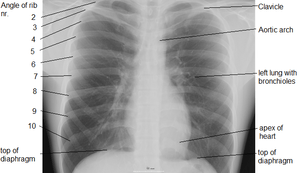

Landmarks

In the average person, the diaphragm should be intersected by the 5th to 7th anterior ribs at the mid-clavicular line, and 9 to 10 posterior ribs should be viewable on a normal PA inspiratory film. An increase in the number of viewable ribs implies hyperinflation, as can occur, for example, with obstructive lung disease or foreign body aspiration. A decrease implies hypoventilation, as can occur with restrictive lung disease, pleural effusions or atelectasis. Underexpansion can also cause interstitial markings due to parenchymal crowding, which can mimic the appearance of interstitial lung disease. Enlargement of the right descending pulmonary artery can indirectly reflect changes of pulmonary hypertension, with a size greater than 16 mm abnormal in men and 15 mm in women.[4]

Appropriate penetration of the film can be assessed by faint visualization of the thoracic spines and lung markings behind the heart. The right diaphragm is usually higher than the left, with the liver being situated beneath it in the abdomen. The minor fissure can sometimes be seen on the right as a thin horizontal line at the level of the fifth or sixth rib. Splaying of the carina can also suggest a tumor or process in the middle mediastinum or enlargement of the left atrium, with a normal angle of approximately 60 degrees. The right paratracheal stripe is also important to assess, as it can reflect a process in the posterior mediastinum, in particular the spine or paraspinal soft tissues; normally it should measure 3 mm or less. The left paratracheal stripe is more variable, and only seen in 25% of normal patients on posteroanterior views.[5]